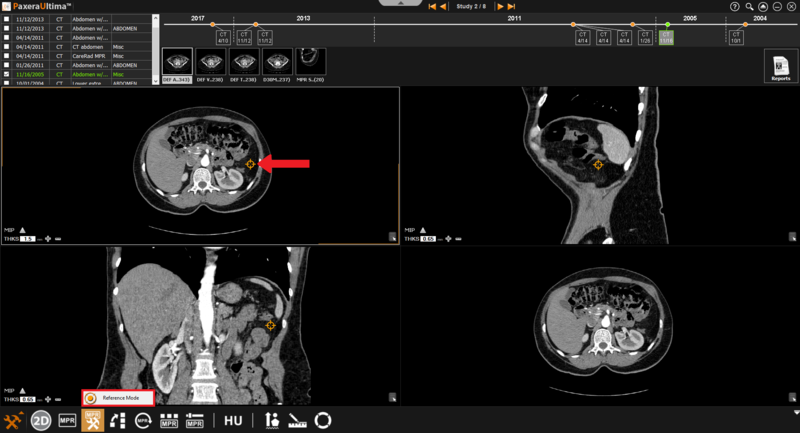

9.4.2. Normal Mode

The normal MPR mode provides three views of the images as shown below:

» Reference mode - this is used when the user needs to refer to a specific point (rather than a specific plane).